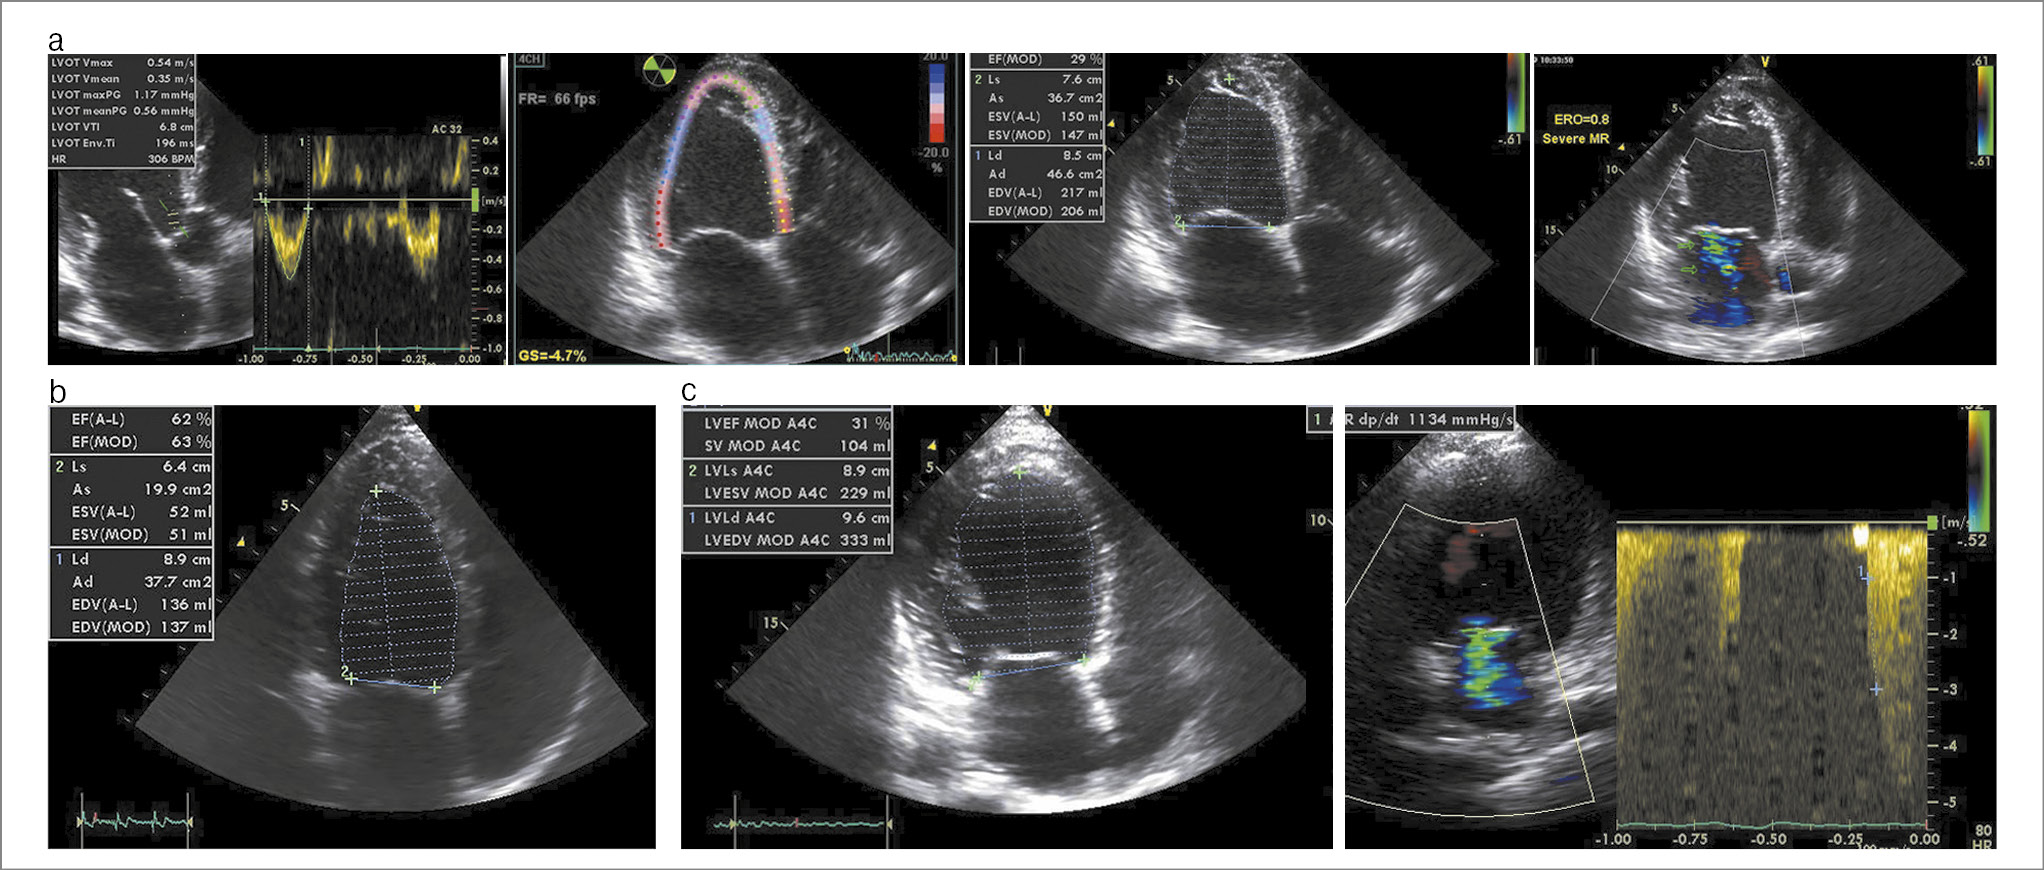

После выписки пациент принимал перечисленную терапию и прекратил употреблять ААС. На фоне лечения отмечал значительное уменьшение выраженности одышки и отсутствие отеков нижних конечностей. В июле 2019 г. при проведении плановой ЭхоКГ (рис. 2, а) отмечена положительная динамика в виде уменьшения выраженности гипертрофии ЛЖ, повышения ФВ ЛЖ до 31%, повышения интеграла линейной скорости в выносящем тракте ЛЖ до 6,8 см, улучшения сократимости правого желудочка (ПЖ). Сохранялись дилатация камер сердца и средней тяжести митральная и трикуспидальная недостаточность (см. табл. 1).

Рис. 2. ЭхоКГ пациента: а – в 2019 г.; b – в 2021 г.; c – в 2024 г.

Пациент продолжил рекомендованное лечение, ААС не употреблял, отмечал отсутствие симптомов СН. В 2021 г. пациенту вновь выполнена ЭхоКГ (рис. 2, b), по данным которой значение ФВ ЛЖ составляло 62%, систолическое давление в легочной артерии – 25 мм рт. ст., толщина стенок ЛЖ уменьшилась до 11 мм (см. табл. 1).

При проведении ЭхоКГ (см. рис. 2, b) выявлено снижение ФВ ЛЖ до 31%, выраженная дилатация камер сердца без наличия локальных нарушений сократимости (см. табл. 1).